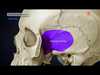

Pterion

H shaped area where 4 bone meets

Frontal, parietal, temporal and sphenoid it is the weakest part of skull

Anterior division of MMA & MMV run behind